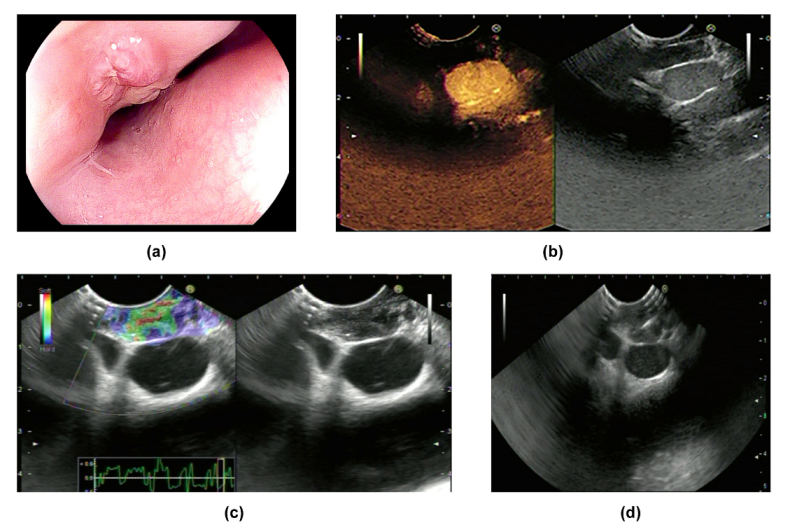

CH-EUS was performed in two cases in our research center. Both lesions featured hypo-enhancement compared with the surrounding tissues (Figure 1b and Figure 2b) (Table 2). Mechanically, hypo-enhancement reflects a deficiency of blood supply, which corresponds to Stage II or above when the lymph nodes undergo caseous necrosis. Caseous granuloma is always detected in infected lymph nodes which are in Stage II or a more severe stage. In fact, granuloma was found in Cases 1–4 which we will introduce later. Using elastography, images of two lesions were mainly green, showing that both lesions were soft (Figure 1c and Figure 2c) (Table 2). The characteristics of ET when using CH-EUS and elastography are worth further evaluation.

8. Case Reports

Figure 2. Manifestations of Case 2: (a) manifestations of the lesion according to EGD; (b) the lesion was hypo-enhanced according to CH-EUS; (c) the lesion was soft according to elastography; (d) EUS-FNA for the lesion.